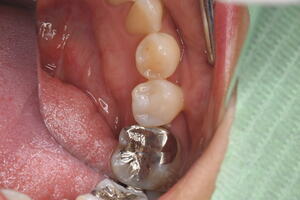

セレックインレーの不適合で虫歯が再発

セレックインレーの破折・ダツリが非常に多いです。出来の悪いセレックインレーが口の中に入っているのをたびたび見かけます。適合の甘いものをセメントでくっつけている。形の悪いものを入れてしまう。

そのせいで磨きにくい状態が出来上がってしまう。その結果、虫歯・再発やダツリを繰り返し歯周病も悪化させてしまうケースが多いです。

適合が悪いため、虫歯が再発 虫歯を取り除き治療終了